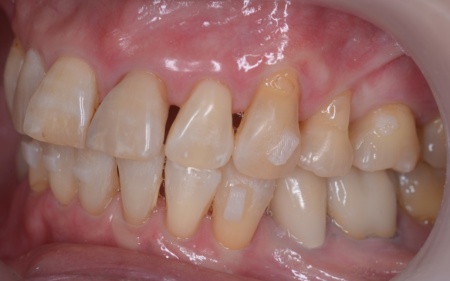

60代女性 すきっ歯が目立つ噛み合わせをワイヤー矯正とアライナー矯正の併用で改善した症例

「以前矯正治療を行ったが、気付いたら前歯がすきっ歯になっていた」とご相談いただきました。

拝見したところ、前歯に隙間が空いており、いわゆるすきっ歯の状態でした。

すきっ歯は見た目の問題だけでなく、食べ物が詰まりやすくなり虫歯や歯周病のリスクが高まる、発音がしにくくなる、噛み合わせが悪化して消化器官や顎関節への負担が増えるなどのおそれがあります。

このまま放置すると、口腔内の環境が悪化して最終的に歯を失いかねないため、早めの治療が必要だと診断しました。